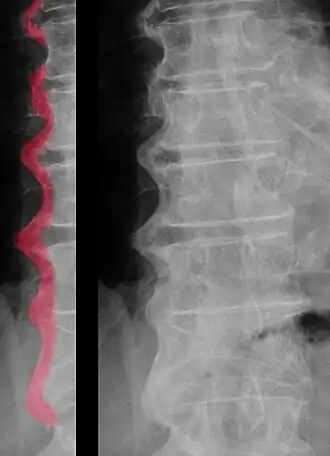

Röntgenfoto van de wervelkolom (thoracaal/lumbaal) met de ziekte van Forestier. Duidelijk is te zien dat de wervels aan elkaar zijn vastgegroeid in een golvend patroon.[1]

- De aanwezigheid van kalk of bot aan de voor- of buitenzijde (anterolateraal) van ten minste vier opeenvolgende wervels. De vorm van deze kalk of botvorming is veelal golvend (zie afbeelding), echter dit is niet noodzakelijk voor het vaststellen van de aandoening.

Bij radiologisch onderzoek kan in een vroeg stadium overmatige botafzetting gezien worden aan de voorzijde van de wervels. Langzaamaan worden dit uitstulpingen die de intervertebrale ruimte overspannen. Hierdoor ontstaat een kenmerkend golvend patroon dat men bij een zijwaartse opname kan zien. De botafzettingen kunnen zowel grof als vloeiend zijn en de dichtheid van de botafzettingen kan sterk verschillen. De botafzettingen kunnen onderbroken worden door minder dichte delen, dit zijn uitstulpingen van de tussenwervelschijf.[19]

- ↑ Afbeelding dr. Jochen Lengerke, 15 september 2009